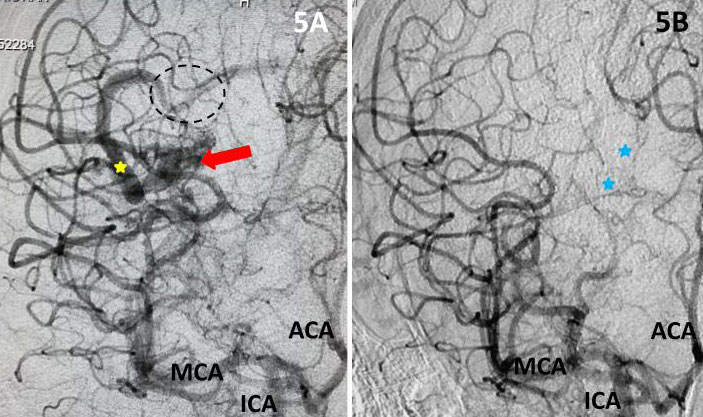

The student underwent NBCA-embolization of the AVM via the dominant feeding posterior cerebral artery with care to avoid embolizing the calcarine branches and avoid NBCA penetration into the single draining vein (Fig 4 and 5). Following the intervention, a tiny feeder from the middle cerebral artery remained (Fig 4).

Fig 5. Comparison, pre (5A) and post-embolization (5B) AP view, late-arterial phase of a right internal carotid artery (ICA) injection. On the right, near total obliteration of the AVM (red arrow). Draining vein (yellow star), residual veins (blue stars).